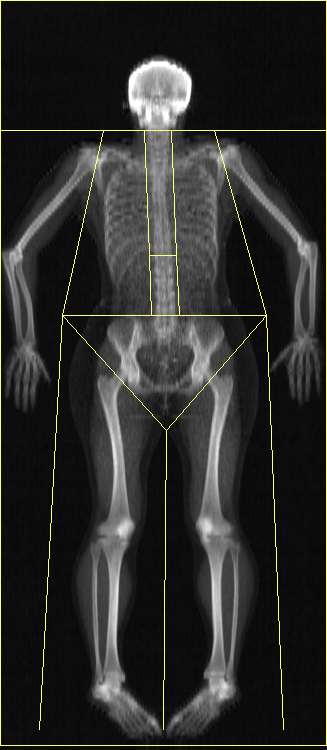

DEXA Scan Lean Mass

Your lean mass and how it's distributed across your body can be useful if you are trying to balance your muscle groups, or partake in particular activities that require higher regional concentrations.

Abnormally low muscle mass can also lead to increased risk of fractures, dementia, and metabolic disorders including Type 2 diabetes.

Imbalance

The charts below show your muscle symmetry from left to right.

Left Imbalance Right

Arms 2.278 kg

2.361 kg

Legs 7.445 kg

7.757 kg

DEXA Scan Body Composition Results

Lean Mass % Lean

Left Arm 2.278 kg 63.1

Right Arm 2.361 kg 61.4

Trunk 24.761 kg 74.4

Left Leg 7.445 kg 65.5

Right Leg 7.757 kg 65.0

Subtotal 44.601 kg 69.6

Head 2.651 kg 66.7

Total 47.252 kg 69.5

Fat Mass % Fat

18.476 kg 27.2

¹ Android (Belly), Gynoid (Bum, hips and thighs) are sub-regions of the body, whose fat masses are already included in the Sub-total and Total figures.

² Total Mass = Lean Mass + Fat Mass + Bone Mass.